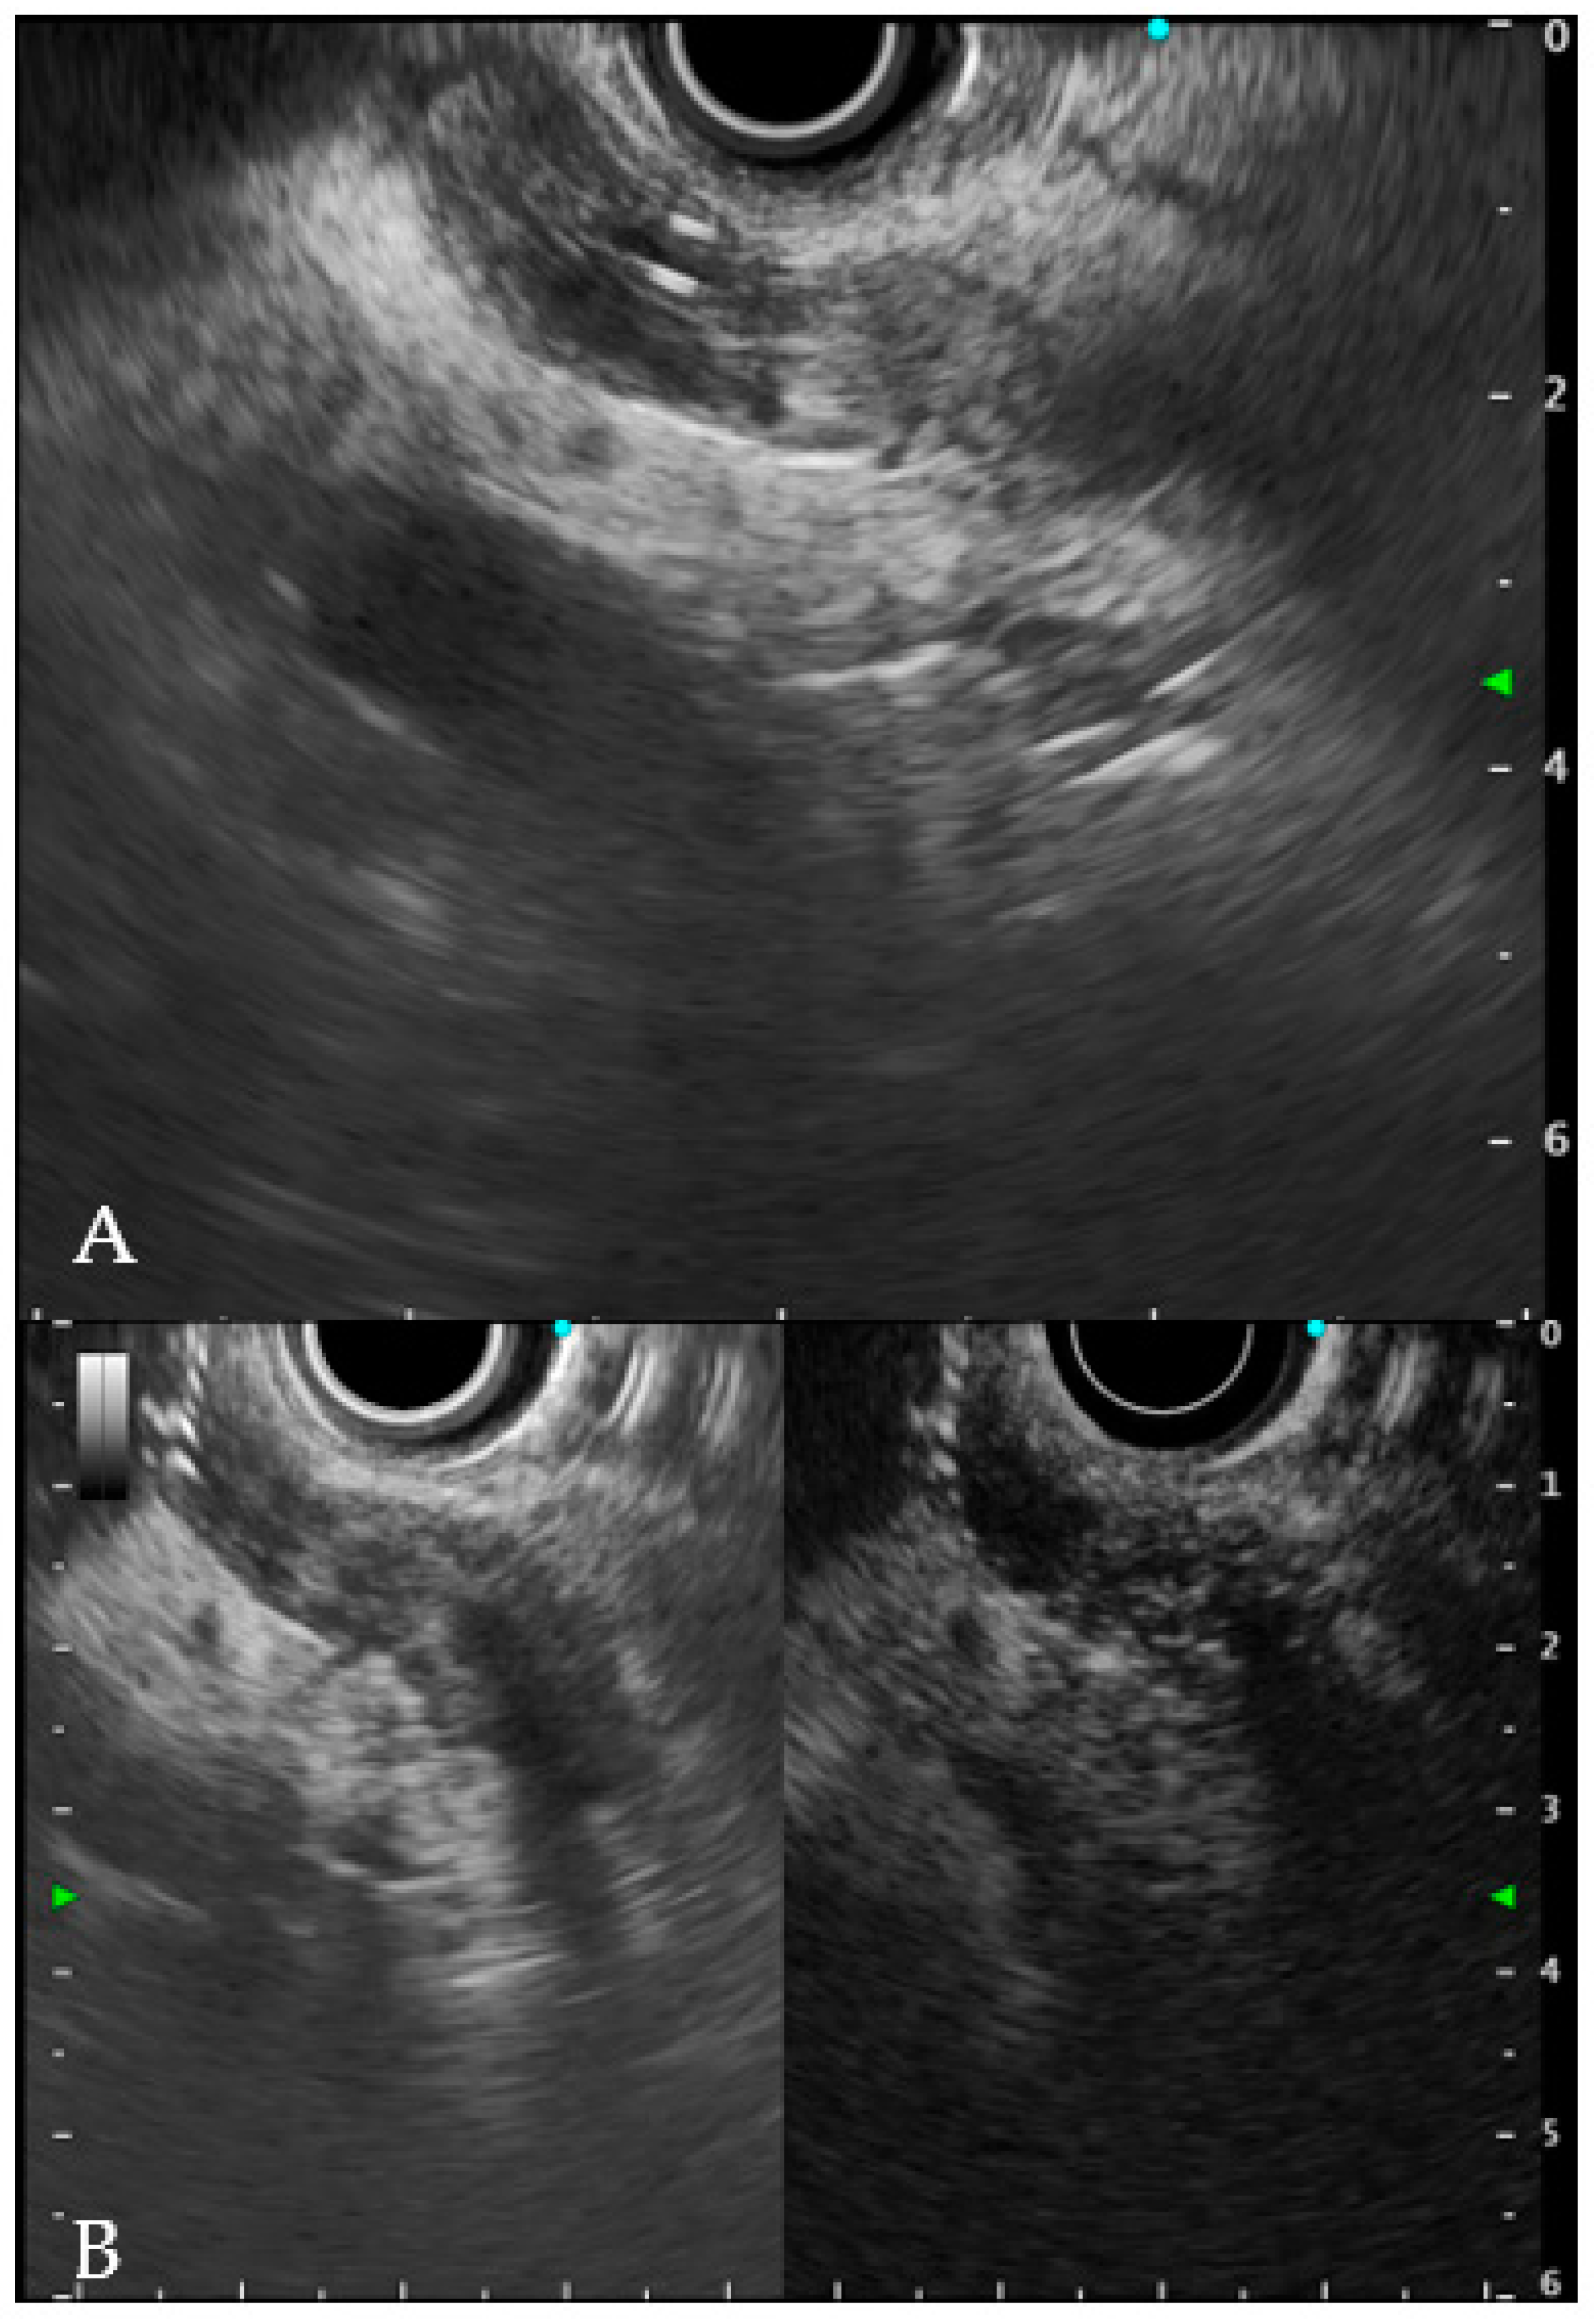

6.1. Intraductal Ultrasonography

- Sun, B.; Hu, B. The role of intraductal ultrasonography in pancreatobiliary diseases. Endosc. Ultrasound 2016, 5, 291–299. [Google Scholar] [CrossRef]

- Meister, T.; Heinzow, H.S.; Woestmeyer, C.; Lenz, P.; Menzel, J.; Kucharzik, T.; Domschke, W.; Domagk, D. Intraductal ultrasound substantiates diagnostics of bile duct strictures of uncertain etiology. World J. Gastroenterol. 2013, 19, 874–881. [Google Scholar] [CrossRef]

- Heinzow, H.S.; Kammerer, S.; Rammes, C.; Wessling, J.; Domagk, D.; Meister, T. Comparative analysis of ERCP, IDUS, EUS and CT in predicting malignant bile duct strictures. World J. Gastroenterol. 2014, 20, 10495–10503. [Google Scholar] [CrossRef]